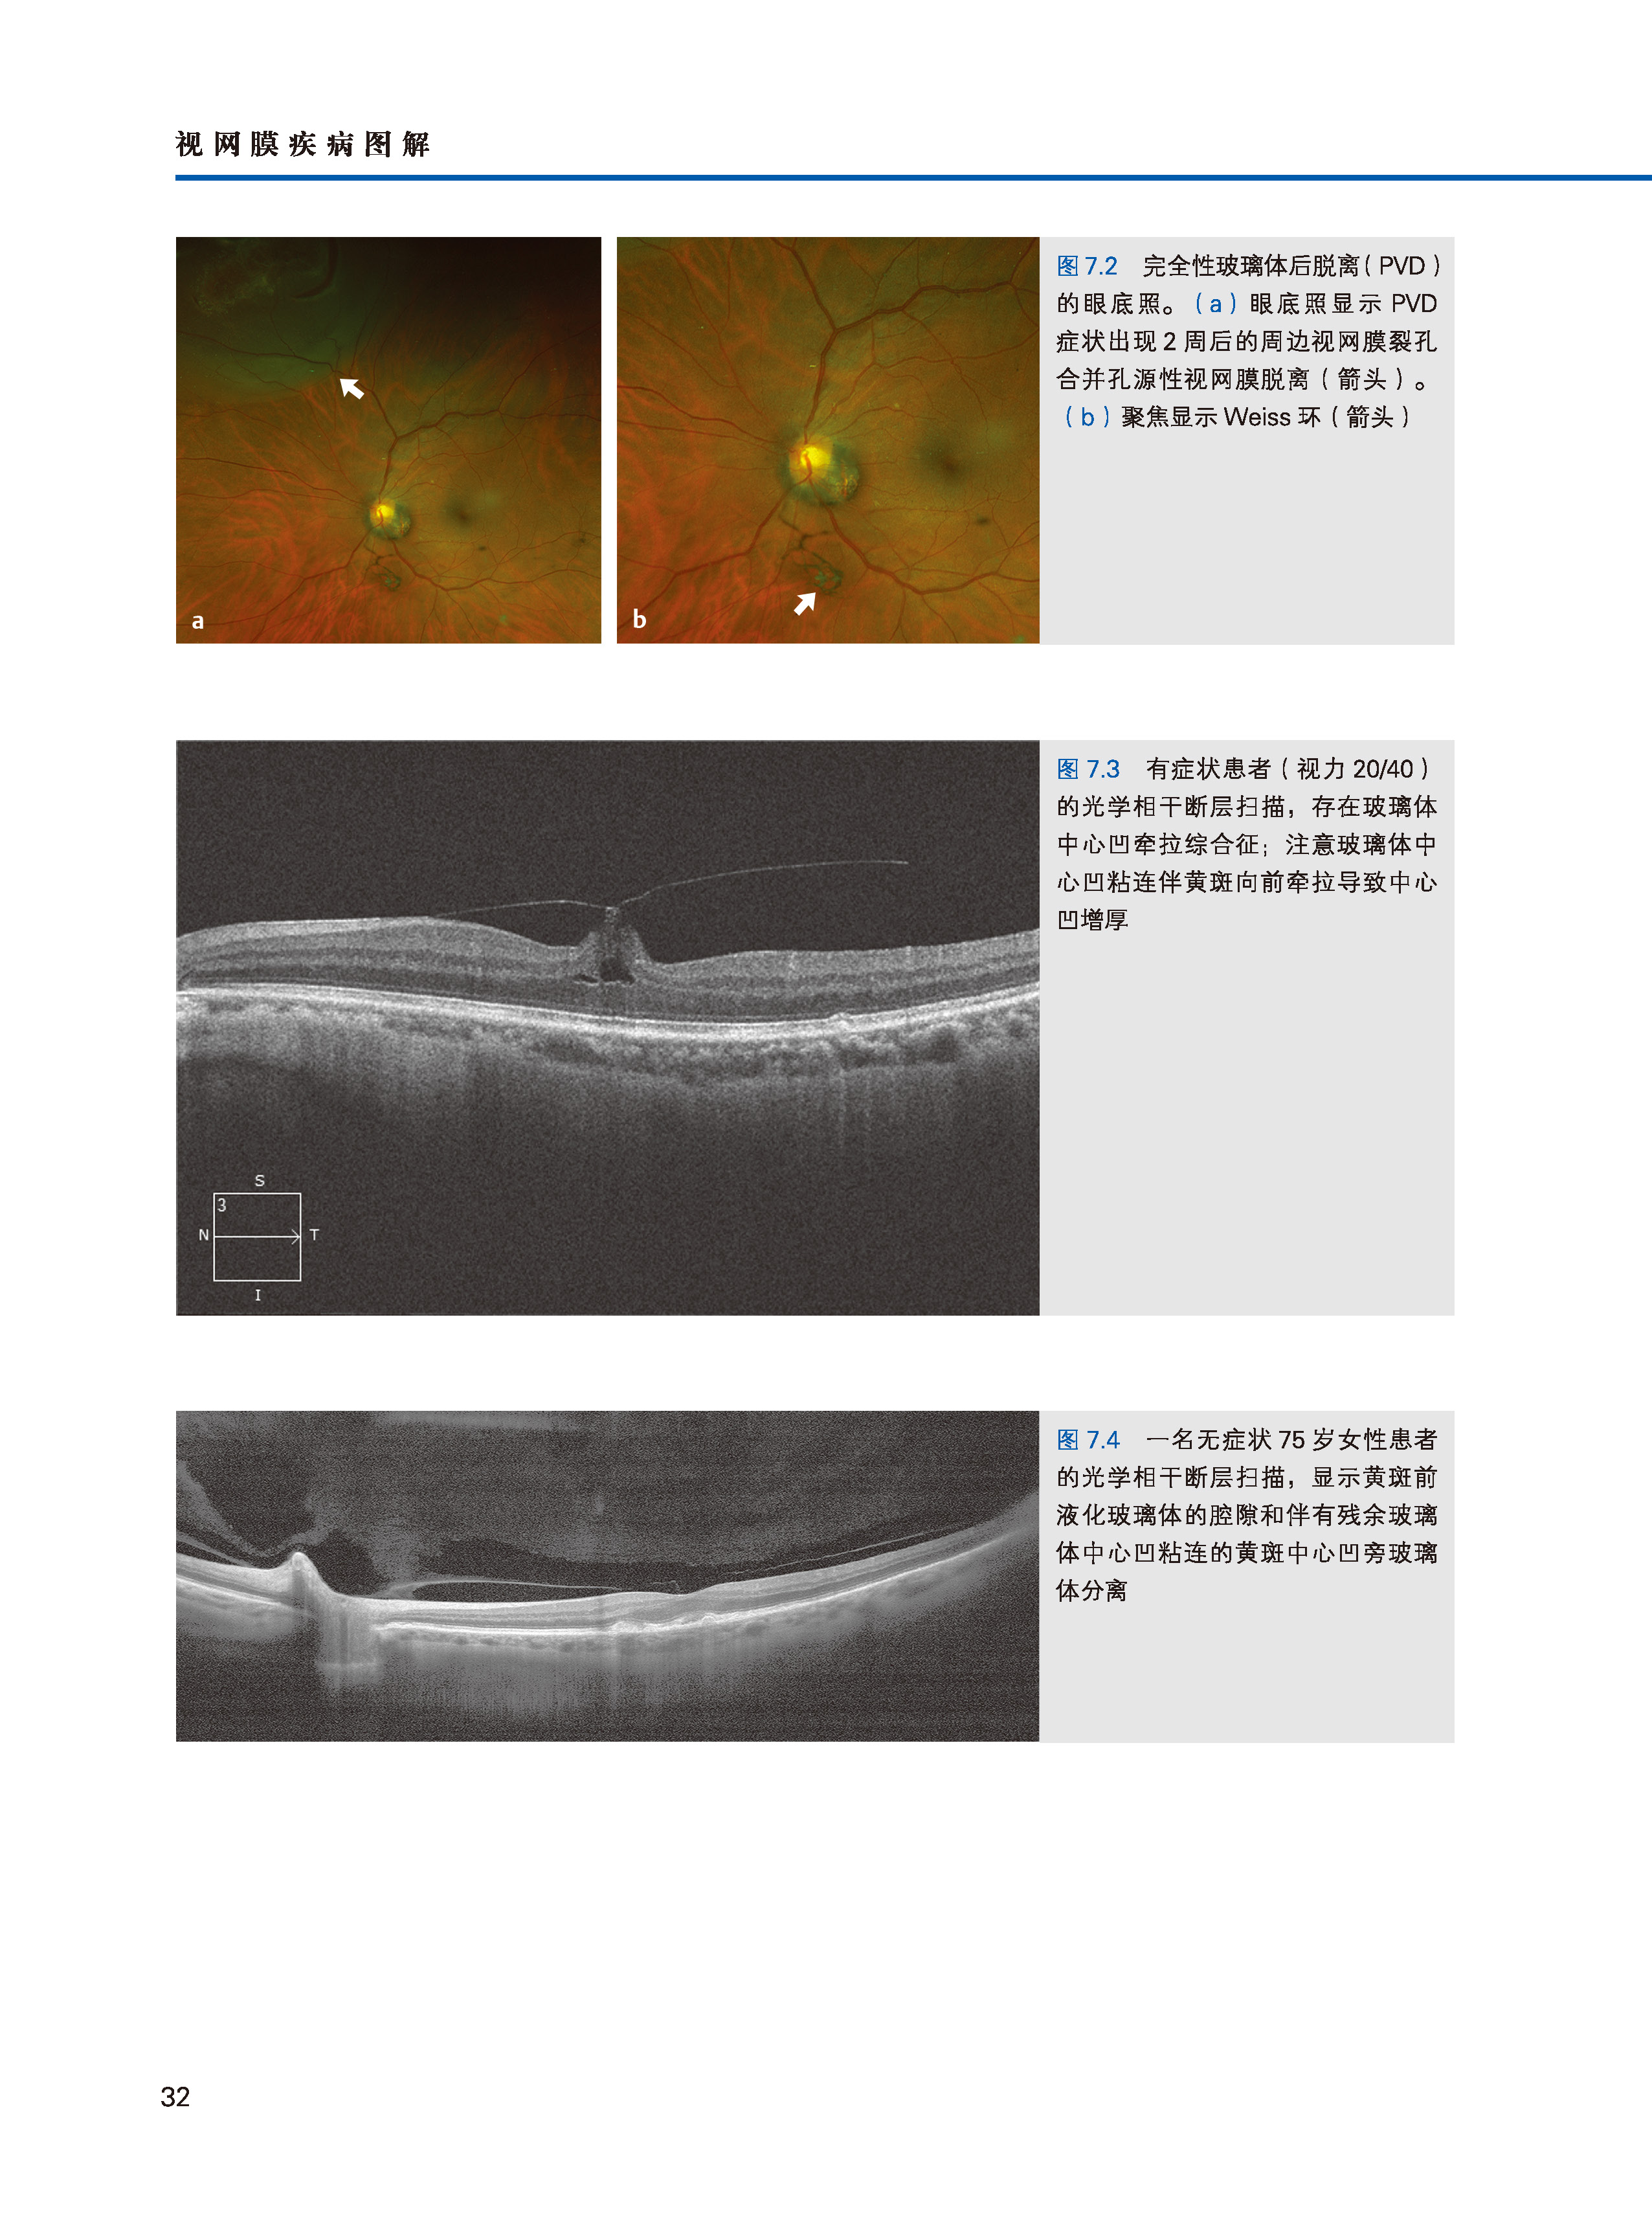

《视网膜疾病图解》由著名眼科专家Justis Ehlers和来自美国、日本、法国、意大利、澳大利亚等国家的几十位著名眼科专家编写而成,分10个部分、102个章节。书中首先讨论了最新的视网膜成像技术,包括超宽视野血管造影,术中光学相干断层扫描和OCT血管成像等;随后分9个部分,介绍了各种视网膜疾病的诊断和治疗,包括变性、血管病变、感染、炎症、创伤、肿瘤和中毒,从主要影响老年人的疾病(如与年龄有关的黄斑变性和脉络膜萎缩)到小儿疾病(如早产儿视网膜病变)。

·介绍了最先进的视网膜成像技术,包括超宽视野血管造影,术中光学相干断层扫描和OCT血管成像等。

·近500幅幅高清视网膜影像资料片,方便使用者对视网膜疾病的理解。